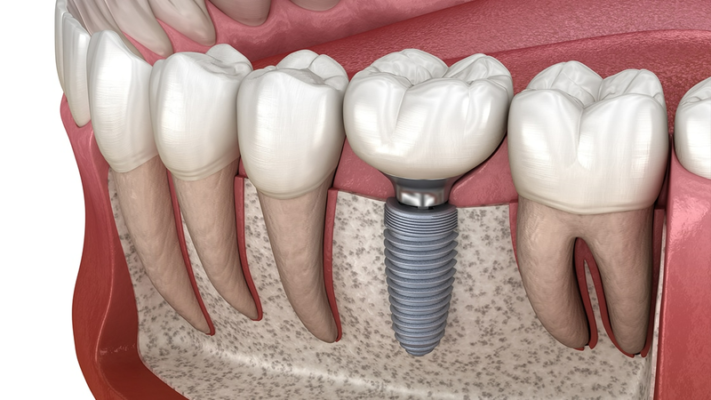

Răng hàm giữ vai trò quan trọng đối với cung hàm, giúp giữ chức năng...

Với sự phát triển của công nghệ nha khoa hiện đại, ngày nay, việc phục...

Trồng răng hàm bị sâu giá bao nhiêu, trong trường hợp răng sâu quá nhiều,...

Răng hàm bị mất dù là răng hàm trên hay răng hàm dưới cũng đều...

Trồng răng hàm bị sâu là phương pháp phục hình răng hiệu quả, giúp răng...

Răng hàm giữ vai trò quan trọng đối với cung hàm, giúp giữ chức năng...

Trồng răng hàm Thái Bình, trồng răng Implant lựa chọn tối ưu hàng đầu trong...

Tình trạng mất răng hàm ảnh hưởng trực tiếp đến quá trình ăn nhai của...

Trồng răng hàm bị sâu là phương pháp phục hình răng hiệu quả, giúp răng...

Khi răng hàm bị mất sẽ gây ảnh hưởng nhiều tới sức nhai từ đó...